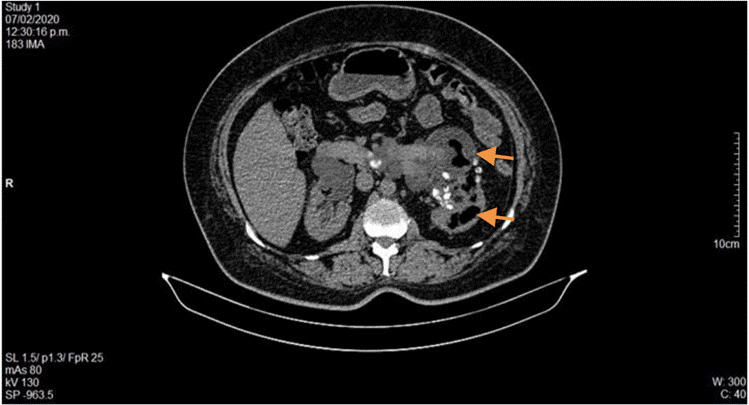

Durante su estancia hospitalaria, el paciente presentó expulsión espontánea de lito, con posterior descenso de azoados desde 2,48 mg/dL de creatinina al ingreso, hasta 1,5 mg/dL, por lo que fue llevado a implante de catéter doble J sin complicaciones. Luego de 21 días de antibiótico, los hallazgos radiológicos (Figura 4) mostraron una disminución de gas en el parénquima renal, por lo cual se le dio el alta hospitalaria y se definió el control para retiro de catéter doble J ambulatoriamente.

La paciente fue valorada por el servicio de medicina interna, el cual consideró hospitalizar con diagnóstico de infección de vías urinarias complicada sin respuesta a tratamiento antibiótico inicial, enfermedad diarreica aguda y enfermedad renal crónica agudizada, por lo que se inició manejo con fluidoterapia, cobertura antibiótica con piperacilina tazobactam, ajustado a función renal (TFG 20,2 mL/min/1,73 m2), y se solicitaron cultivos. Asimismo, se realizó ecografía con evidencia de riñón izquierdo aumentado de volumen, de contornos regulares, con presencia de ecogenicidades puntiformes en el grupo calicial superior con aspecto de gas. Se solicitó UROTAC (Figuras 5 y 6) que reportó gas en el sistema colector del riñón izquierdo, más específicamente en pelvis renal izquierda y dentro del uréter izquierdo, además de anomalía congénita de fusión renal (riñón en herradura), hidronefrosis leve izquierda con pelvis globulosa y múltiples litiasis a nivel de uréter distal y unión ureterovesical izquierda. La paciente tuvo expulsión espontánea de litos y descenso de azoados hasta niveles basales (1,9 mg/dL).

Fuente: documento obtenido durante la realización del estudio.

Figura 5 UROTAC en el que se evidencia riñón en herradura, hidronefrosis leve izquierda y gas distribuido en sistema colector del riñón izquierdo.